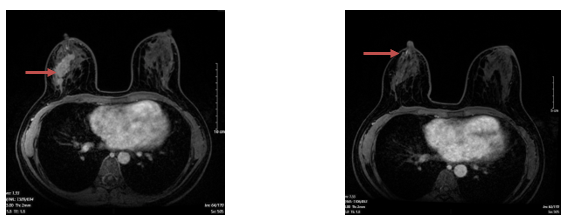

+ Chụp cộng hưởng từ hai bên tuyến vú (03/11/2024)

- Vú phải: vị trí góc 1/4 trên trong có nốt kích thước 5mm ngấm thuốc muộn tăng dần, không thấy thải thuốc.

- Không thấy hình ảnh tụt núm vú, không thấy co kéo da

- Hố nách bên phải, chặng I có vài hạch, có vỏ hạch dày, lớn nhất kích thước 7x13mm

Hình 3. Hình ảnh cộng hưởng từ tuyến vú trước và sau điều trị: Khối u vú giảm kích thước, còn nốt kích thước 5mm, ngấm thuốc sau tiêm (mũi tên màu đỏ

Nhận xét: Sau điều trị 6 đợt hóa chất tân bổ trợ TC kết hợp với Trastuzumab, bệnh nhân cải thiện về lâm sàng và đáp ứng trên phim chụp cộng hưởng từ và siêu âm tuyến vú hai bên (khối u tại vú và kích thước hạch giảm đáng kể). Đánh giá đáp ứng một phần theo tiêu chuẩn RECIST 1.1.